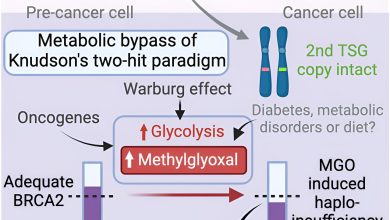

Cientistas descobrem um elo perdido entre uma dieta pobre e um maior risco de câncer

Resumo gráfico. Crédito: Célula (2024). DOI: 10.1016/j.cell.2024.03.006 Uma equipa de investigação da Universidade Nacional de Singapura (NUS) descobriu novas descobertas…